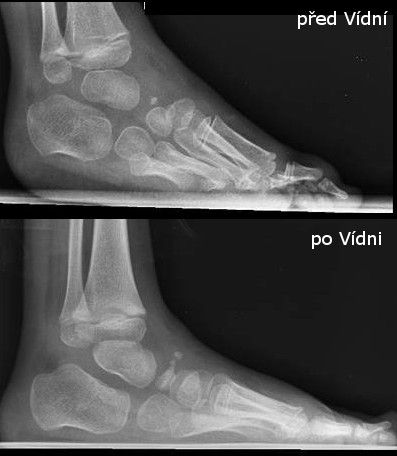

Po růstových spurtech, po 3. roce věku, nastala recidiva a nepomohlo ani cvičení dle Vojty, ani lázně. Zvýraznil se nášlap přes malíkovou hranu a dívka začala postupně chodit jen po špičce nohy.

Viditelně nedošlapuje na paty

Dorsiflexe v minusových hodnotách

Bylo potřeba začít úplně od začátku – znovu 5 sáder (konečně správně dle Ponseti metody) a opět udělat malý operační zákrok (tenotomie).